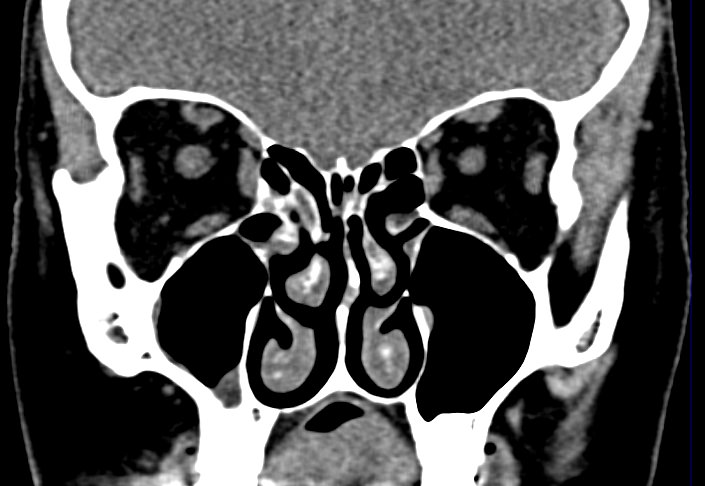

Золотым стандартом в диагностике патологических процессов пазух носа является мультиспиральная компьютерная томография, которая является быстрым безболезненным и неинвазивным (то есть без вмешательства в организм) способом исследования состояния синусов. Метод основан на проникающей способности ионизирующего излучения и получения изображений органов и тканей организма за счет разной степени поглощения ими рентгеновских лучей.

На основе полученных данных цифровые приложения томографов создают трехмерные реконструкции пазух носа, что позволяет оценить пространственное взаимоотношение анатомических структур и помогает в диагностике патологии околоносовых пазух.

Мультиспиральная компьютерная томография дает информацию о состоянии полости носа, носовой перегородки, степени воздушности околоносовых пазух, путей дренирования синусов, состоянии слезных каналов. Сканирование позволяет оценить толщину слизистой, наличие патологического содержимого в просвете пазух (уровня «жидкости»), выявить опухолевые образования. С помощью КТ можно провести точную диагностику травматических повреждений костей лицевого черепа, определить локализацию инородных тел, попавших в полости синусов.

С помощью объемной реконструкции можно перед оперативным вмешательством увидеть особенности анатомии ЛОР-органов, определить точное расположение патологического очага по отношению к окружающим тканям. Компьютерная томография помогает в диагностике аномалий развития придаточных пазух носа, слезоотводящих каналов.